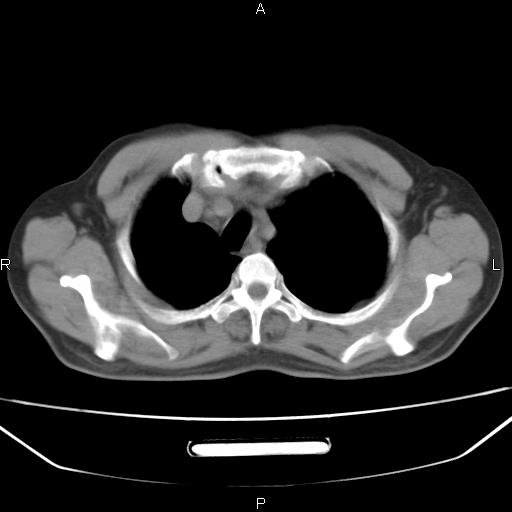

患者,男。50岁。近几日有咳嗽症状,无其他不适,既往病史无,考虑膈疝。请前辈们看看指导指导。

膈膨升,左下肺通气不良,膈肌好像还完整。

考虑左侧膈疝。

左侧膈疝。

符合隔膨升,膈肌较完整。